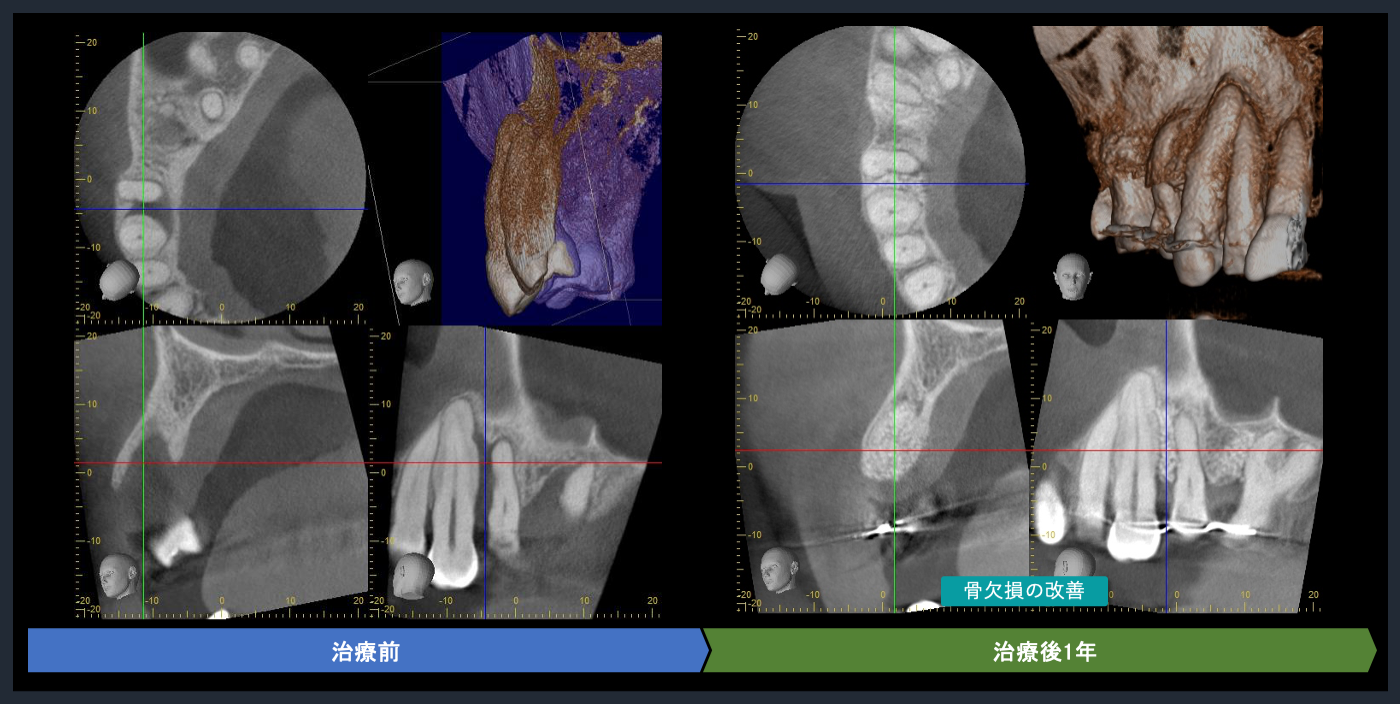

| 概要 | 歯周病が進行しており、右上臼歯部に重度の骨吸収像が認められます。失われた骨を再生し、歯の生存率を高めることを目的に、再生療法を試みました。良好な結果を得ることができました。問題なく使っていただいております。 再生療法を行う利点としては、ポケットが浅くなるので、患者様ご自身でのブラッシングで管理し、コントロールすることが可能になります。もちろん定期的なメインテナンスは必要不可欠です。 |

CTでの術前診査1

歯周基本治療後の再評価

Post-treatment evaluation

Post-treatment evaluation

CTでの術前診査2